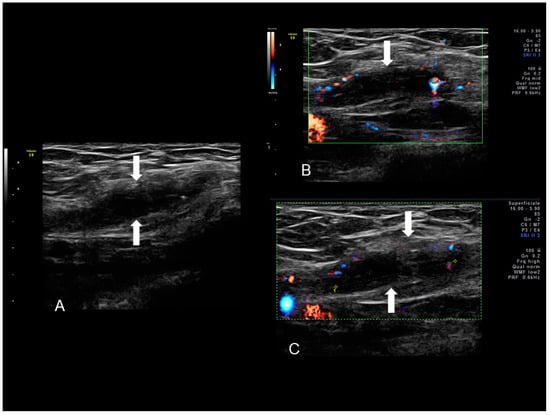

Figure 9. Sonographic features of right inguinal endometriosis (see white arrows) (A) presenting as a cystic mass with internal septa, hypoechoic content and few peripheral color spots located in inguinal area due to a scanty vascularization (B,C).

Inguinal endometriosis is quite variable in its ultrasonographic presentation. It may appear as a completely solid mass (Figure 9) or a mixed solid and cystic mass (Figure 10). Cystic masses can be hypo or hyperechoic [22] and usually there is evidence of peripheral vascularization at Doppler evaluation (Figure 9).